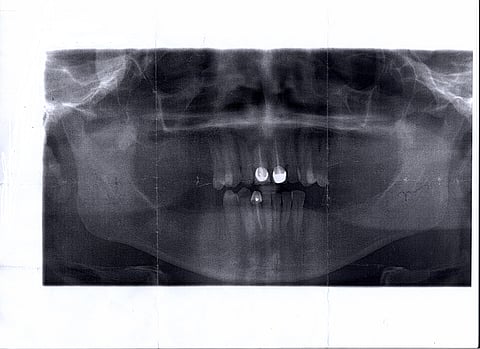

عيسى الحربي- سبق- الرياض: ناشد الشاب "ح. ش" أهل الخير، سداد فاتورة العملية الجراحية المقررة لزراعة كامل الأسنان في الفكين، مشيراً إلى أنه يواجه صعوبة في المضغ، وإحراجاً أمام الناس؛ لخلوّ فمه من أي "سن"، على الرغم من صغر سنه.

وقال لـ"سبق" إن العوز وضيق ذات اليد حرمته من زراعة الأسنان، في حين يستبشر كل يوم بانفراج المعاناة، وإعادة الأمل، بعد أن زفّ الطبيب المعالج إمكانية نجاح التركيب والزراعة بنسبة عالية.

وأضاف: "عانيت من الاستمتاع بالأكل، وأيضاً الكلام، لسنوات طويلة؛ بسبب العيب الخلقي في الفم، وهشاشة الأسنان التي قضت على جمالية الوجه، ومبلغ العملية الضئيل بالنسبة للقادرين كافٍ ليجعلني أعيش بقية حياتي أسوة بغيري، ممن يتمتع بأنياب وقواطع وأسنان وضواحك".